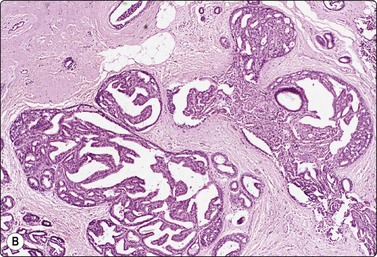

image image

Fig. 7.14 Cystic carcinoma

(A) Obviously malignant epithelial cells with a background of debris in aspirated fluid (MGG, HP); (B) Tissue section showing malignant cells lining the cyst wall (H&E, HP).